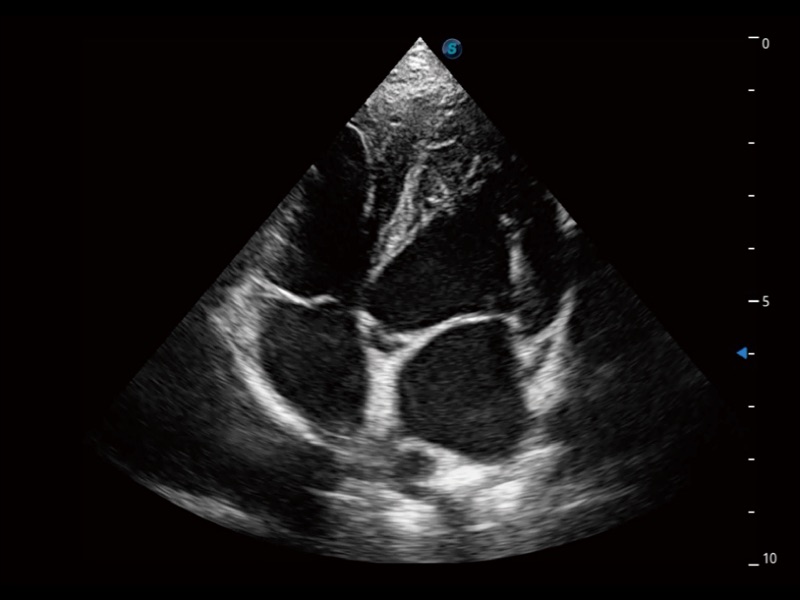

• Auto EF 心内膜自动描迹

能够基于左心室壁追踪和辛普森法,自动计算射血分数,支持多个可移动点描迹,与手动测量相比,极大节省了动物医生的时间和精力。

• Stress Echo 负荷超声心动图

具备多种协议可选,同时支持17阶段划分法和专业的SE报告。

• AMM 解剖M型

通过360度任意调节3条M型取样线,在同一心动周期上观察心脏不同位置的运动曲线,得到准确的心功能测量数据,有效评估心肌运动及左心室功能。

• TDI 组织多普勒成像

实时用颜色表示心肌组织运动,观察和定量组织的运动情况,对快速检测与评估心肌的灌注和活性、电传导及心肌收缩和舒张功能等均能提供重要的诊断信息。

(犬)四腔心

(犬)四腔心MQA